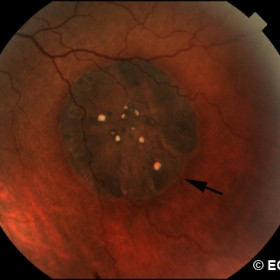

Hypertrophy of the retinal pigment epithelium

Hypertrophy of the retinal pigment epithelium - Flat, black with peripheral halo (arrow)